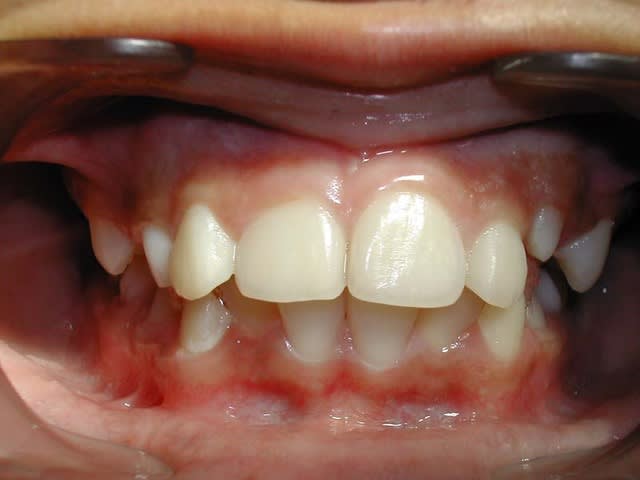

Puisque vous insistez tant :

Voici les Rx. du cas adulte. Pour les photos, ce sera un peu plus tard.

Face op1hnm - Eugenol